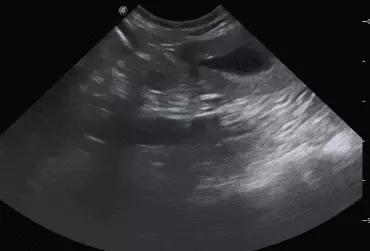

W literaturze opisano niewiele przypadków ciąż bliźniaczych jednokosmówkowych u suk. W trakcie wczesnej diagnostyki ultrasonograficznej ciąży u suki rasy whippet (chart angielski) zobrazowano pęcherz ciążowy, w którym znajdowały się dwa zarodki. Podczas badań kontrol­nych zarodki, a później płody wykazywały prawidłową organogenezę i żywotność. Ich rozwój przebiegał podobnie względem pozostałych ośmiu płodów. W 63. dniu ciąży wykonano zabieg cesarskiego cięcia i wydobyto dwa płody tej samej płci, o bardzo podobnym wyglądzie, z dwóch pęcherzy płodowych przyczepionych do jednego łożyska, oraz pozostałe osiem płodów.

Ryzyko związane z ciążą bliźniaczą jednokosmówkową u ciężarnych suk nadal jest nieznane, istnieją jednak doniesienia o śmierci płodu lub płodów w ciążach jednokosmówkowych u tego gatunku. Badanie ultrasonograficzne w czasie ciąży pozwala na wczesne rozpoznanie ciąży jednokosmówkowej, a monitorowanie żywotności płodów może ograniczyć ryzyko powikłań położniczych i przynieść korzyści zdrowotne zarówno samicy, jak i rodzeństwu z miotu.